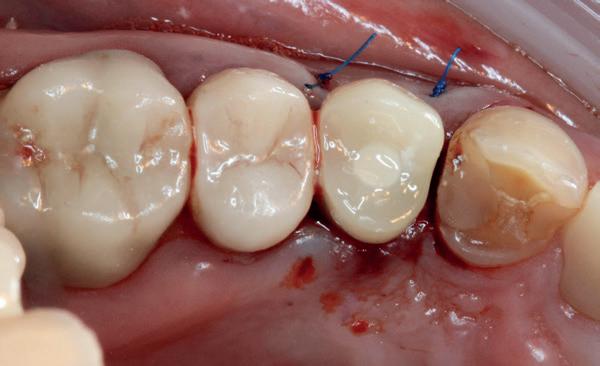

Het kantelpunt: de patiënt komt terug (afbeelding 14-16)

De patiënt meldde zich opnieuw in de praktijk met klachten: pijn, zwelling en een duidelijke intraorale infectie. Bij inspectie zag ik direct een probleemhet ging om een klassiek beeld van peri-implantair botverlies met een abces. Dit patroon van botverlies en infectie spiegelde sterk de gevolgen van thermische trauma.

Op de röntgenfoto’s zag ik wat ik al vreesde: er was botresorptie rond het implantaat. De zachte weefsels waren ontstoken en het implantaat vertoonde teke-

nen van mobiliteit. Op dat moment wist ik precies wat er was misgegaan.

Dit was geen kwestie van een verkeerde occlusie of een slecht gekozen abutment. Dit was een puur biologisch probleem, veroorzaakt door mijn onderpreparatie van de osteotomie en de daarmee gepaard gaande botnecrose of compressie. Mijn streven naar immediaat belasten had me verblind, en ik had een fundamentele regel van de implantologie genegeerd: bot moet kunnen ademen. Op dat moment had ik geen andere keuze dan de situatie te herstellen.